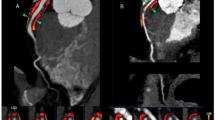

Computed tomography coronary angiography (CTCA) provides a non-invasive method to evaluate coronary artery disease that allows the phenotyping of atherosclerotic plaques and surrounding perivascular adipose tissue (PVAT).

Certain atherosclerotic plaque characteristics (such as positive remodelling, non-calcified plaque, spotty calcification and the napkin-ring sign) are indicative of an increased risk of adverse coronary events; quantitative plaque assessment might help to identify patients at high risk, beyond traditional assessments of stenosis severity.

Kwiecinski, J. et al. Noninvasive coronary atherosclerotic plaque imaging. JACC Cardiovasc. Imaging 16, 1608–1622 (2023).